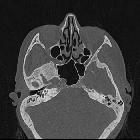

CT is usually the best modality to assess these masses.

CT

- soft tissue mass lateral to the cochlear promontory

- if large may fill the middle ear cavity, and invade the Eustachian tube or mastoid

- ossicles may or not be destroyed and may simply be encased

- surrounding bony destruction may be present in aggressive tumours

- intact jugular bulb